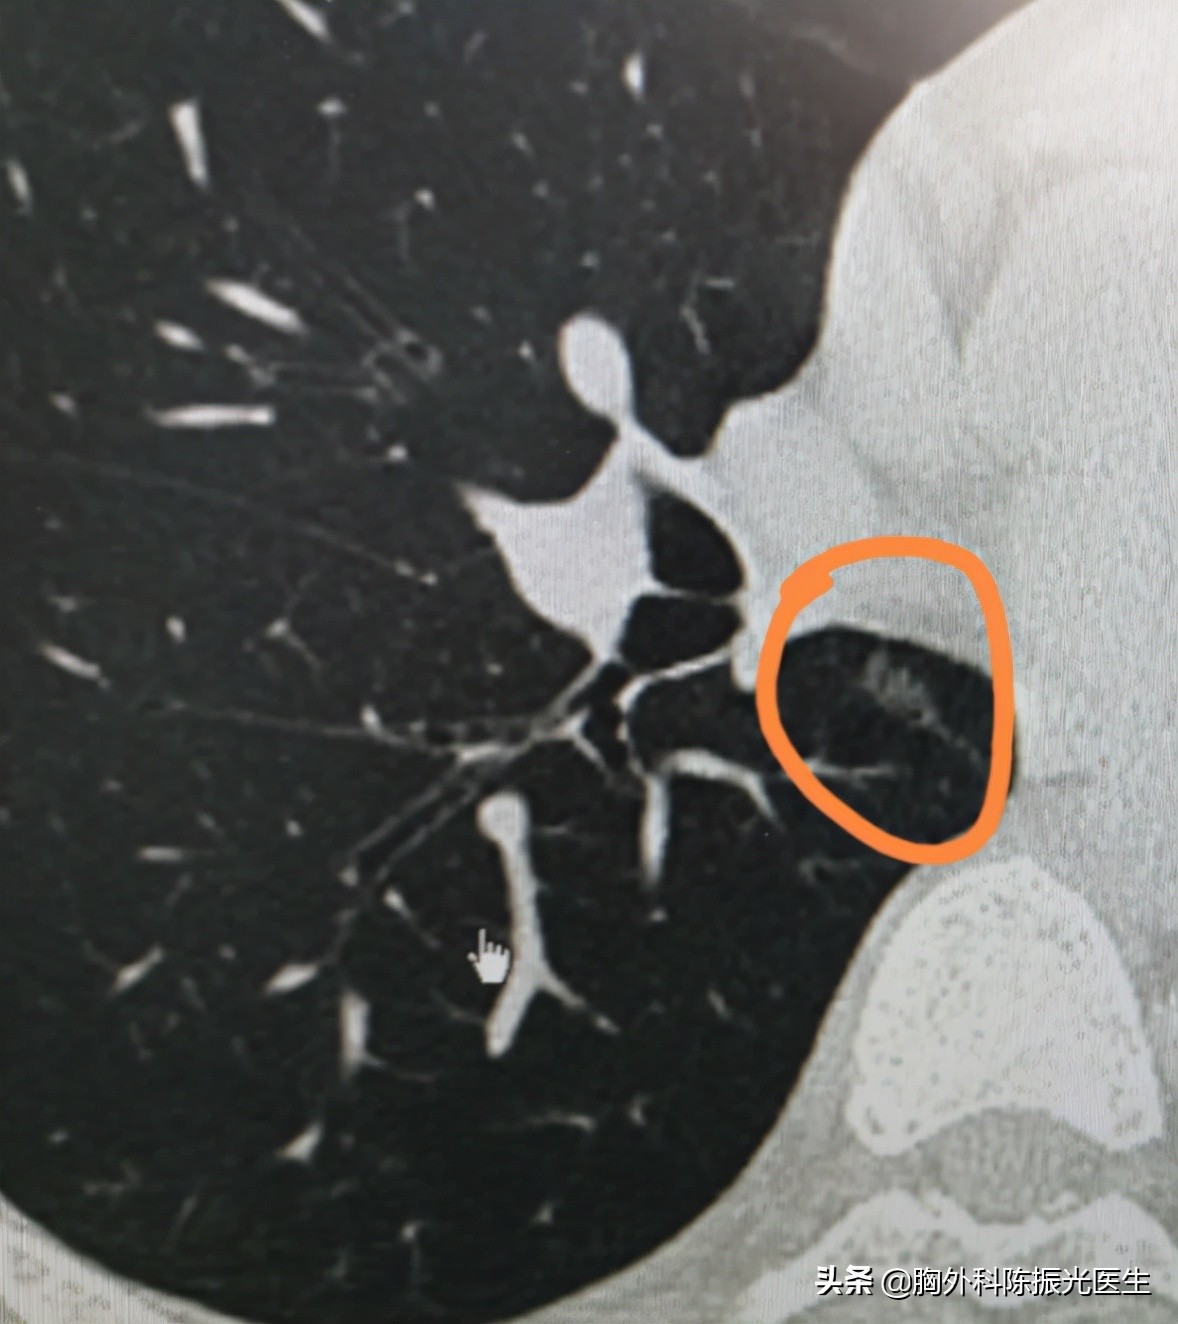

“我最近体检胸部CT平扫检查,发现左肺上叶前段与上舌段交界处、右肺下叶背段这两个地方,各发现一个磨玻璃密度结节影,大小分别是8毫米x 6毫米、8毫米x 5毫米,同时右肺下叶背段发现一个实性小结节,直径4毫米,同时检查血肿瘤标志物NSE稍稍高了一点,是不是长了肺癌?”

“您的这两个结节,虽然已经达到8毫米,但是性质上来说还需要进一步观察,尤其是动态观察结节大小形态的变化走势,目前并不能诊断肺癌。”